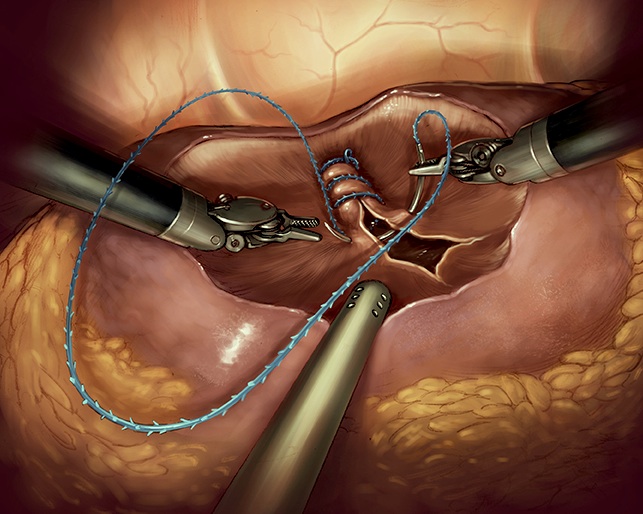

NEFRECTOMIA LAPAROSCOPICA Y ROBOTICA

La cirugía convencional del riñón se hacía “a cielo abierto”, pero hoy en día en la mayoría de los centros más avanzados ha pasado a realizarse por laparoscopia.

Consiste en realizar pequeñas incisiones abdominales de medio a un centímetro, por las que se introducen pinzas y tijeras especiales y una cámara que permite operar mirando una pantalla.

Con esta novedosa técnica logramos la misma o mejor precisión en la curación del tumor y, al evitar las grandes incisiones de la cirugía abierta, el paciente tiene mucho menos dolor postoperatorio, y puede abandonar el hospital al día siguiente a la intervención y reincorporarse antes a su vida habitual.